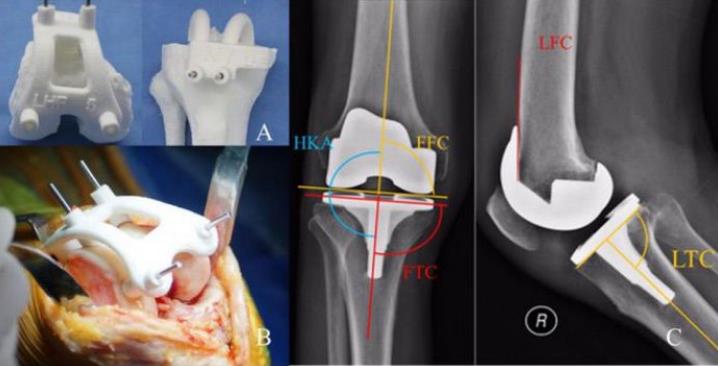

家屬了解情況后,立即給阿婆辦理了住院手續。骨一科主任李松軍在得知情況后,立即讓管床醫生快速完善了術前檢查,并利用下肢CT數據進行建模,3D打印個性化手術導板。檢查結果出來后,發現阿婆心功能極差,心臟射血分數只有40%(正常值為50%-70%),且有房顫伴預激綜合征、高血壓、糖尿病、多發腔隙性腦梗死等多種基礎疾病,手術風險非常高。這種情況進行膝關節置換手術,術中心臟一旦承受不住,就可能出現生命危險,手術必須快速完成,且保證術中盡可能出血少,減少心臟負荷。

如何安全快速且保質完成手術?李松軍主任團隊經過反復研究術前資料、術前3D導板設計打印、術前手術規劃,以及詳細的圍術期準備后,7月11日,鐘阿婆的手術順利完成。

3D打印手術導板引導下人工膝關節置換有什么優勢?

傳統膝關節置換術的截骨依賴于通用截骨組件進行,即使精準的傳統截骨器械,與實際解剖相比準確性僅約為 75%,加之截骨組件的磨損、術者經驗不足、解剖變異和膝關節畸形等情況,都會導致截骨偏差進一步加大,進而可能導致手術效果不佳而降低患者術后的生活質量,甚至短期內即需要進行翻修手術,給患者帶來痛苦的同時也造成醫療資源的浪費。

基于患者個人CT檢查數據,3D打印制定個性化手術導板,真正做到個體化、精準化,可獲得良好的匹配性和精準的假體對線、對位,從而獲得良好的手術效果及假體使用期限,并減少手術時間、減少出血、有效防止嚴重并發癥的發生。